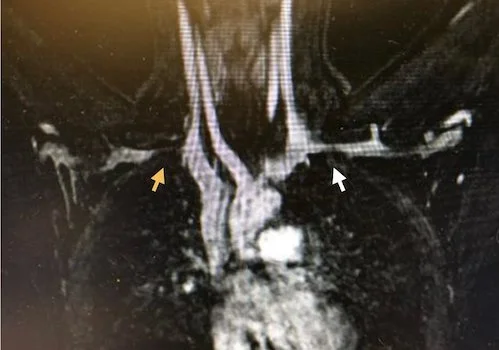

<p>O diagnóstico é baseado em uma combinação de história clínica, exame físico e exames de imagem. Testes específicos durante o exame físico, como a manobra de abdução com rotação externa do ombro, podem reproduzir os sintomas. Exames de imagem, como a ressonância magnética ou a angiografia por tomografia computadorizada, são úteis para visualizar a compressão do nervo e da artéria e avaliar a presença de qualquer anomalia anatômica. A condição pode ser subdiagnosticada e não valorizada em exames de imagem se não houver fraqueza clínica significativa.</p>

<p><strong>Exemplo de Laudo de Ressonância:</strong>

"Observa-se atrofia do músculo redondo menor, sugerindo possível compressão crônica do nervo axilar no espaço quadrangular."</p>

<p>Ressonância magnética demonstrando atrofia do redondo menor</p>